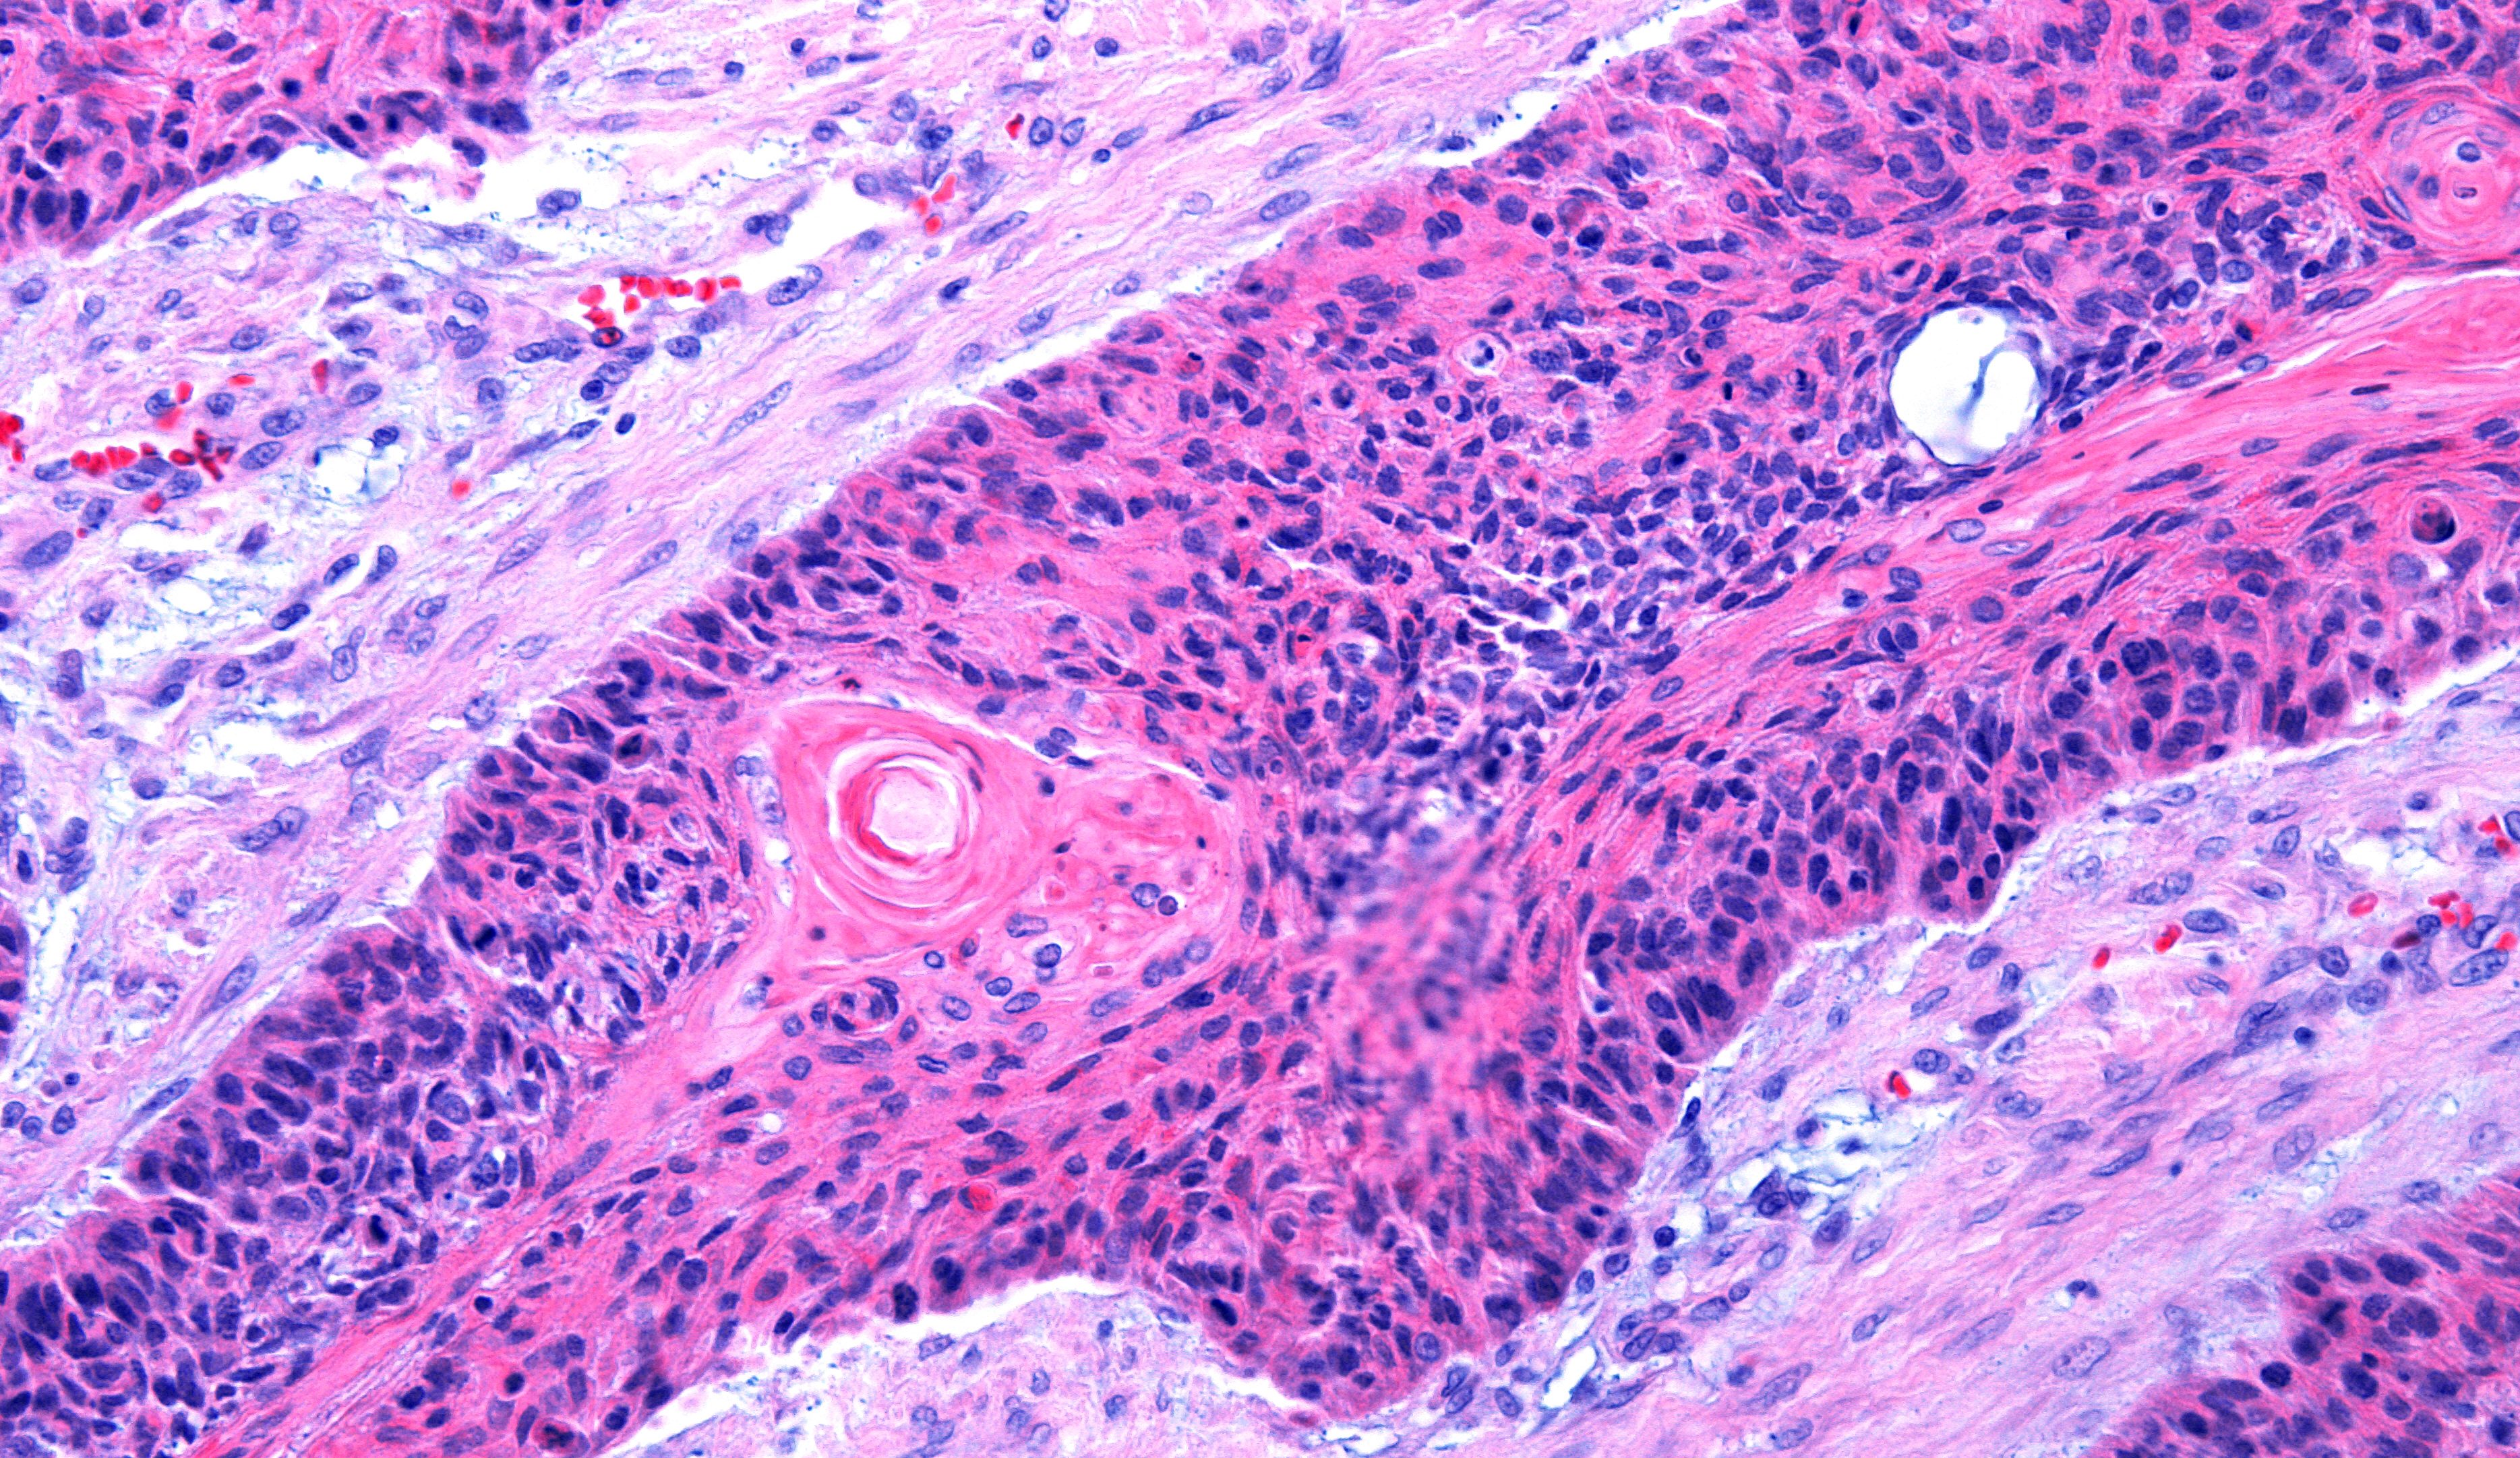

cSCC arises from an aberrant proliferation of keratinocytes, often in sun-damaged skin. While surgery is typically effective, a subset of tumors metastasize, and many patients, particularly the elderly or immunocompromised, present with numerous precancerous lesions. Current treatments, like chemotherapy and some targeted therapies, have limitations. This new topical cream offers a different strategy: activating the immune system within the skin itself.

The cream functions by inhibiting LSD1, an enzyme that normally suppresses immune-activating pathways in epidermal cells. By blocking LSD1, the cream essentially ‘lifts the brake’ on the immune response, encouraging skin cells to recruit immune cells – specifically CD4⁺ T cells – to attack the tumor. Experiments demonstrated that blocking retinoic acid signaling reversed the cream’s effects, and eliminating CD4⁺ T cells removed the tumor-suppressing benefit, confirming the importance of the skin-immune system interaction.